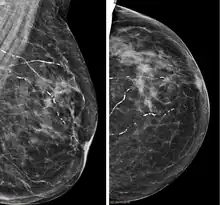

Right breast mammograms showing several calcified arterioles. Patient 94 years old. | |